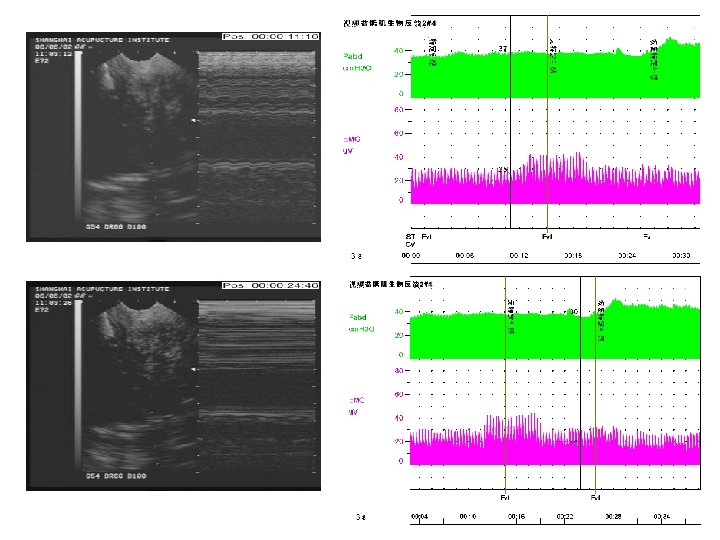

• Electrical pudendal nerve stimulation • After the needling sensation referred to the above regions was produced, a G 6805 -2 Multi-Purpose Health Device was connected with the inserted needles used as electrodes. The device was set to produce an electrical stimulation at a frequency of 2. 5 Hz (150 times/min) and an intensity as high as the patient could tolerate without discomfort. The electroacupuncture was set for 60 minutes each time. • 3. 电针阴部神经刺激疗法 • 针感达特定部位后接G 6805Ⅱ治疗仪。电针采 用连续波,频率约 2. 5 Hz (150次/分),强刺激 以患者不感到难受为度,每次持续 60分钟。

• Electrical pudendal nerve stimulation • Strong rhythmic and cephalad contraction of the pelvic floor muscles around the urethra must be kept during the electroacupuncture. • The treatment was given once every other day. The treatment course was based on the patient’s condition. • 电针期间需保持盆底肌以尿道为中心有节律地 向上(头部方向)强烈收缩的感觉。 • 治疗隔日 1次,治疗次数视病情而定。